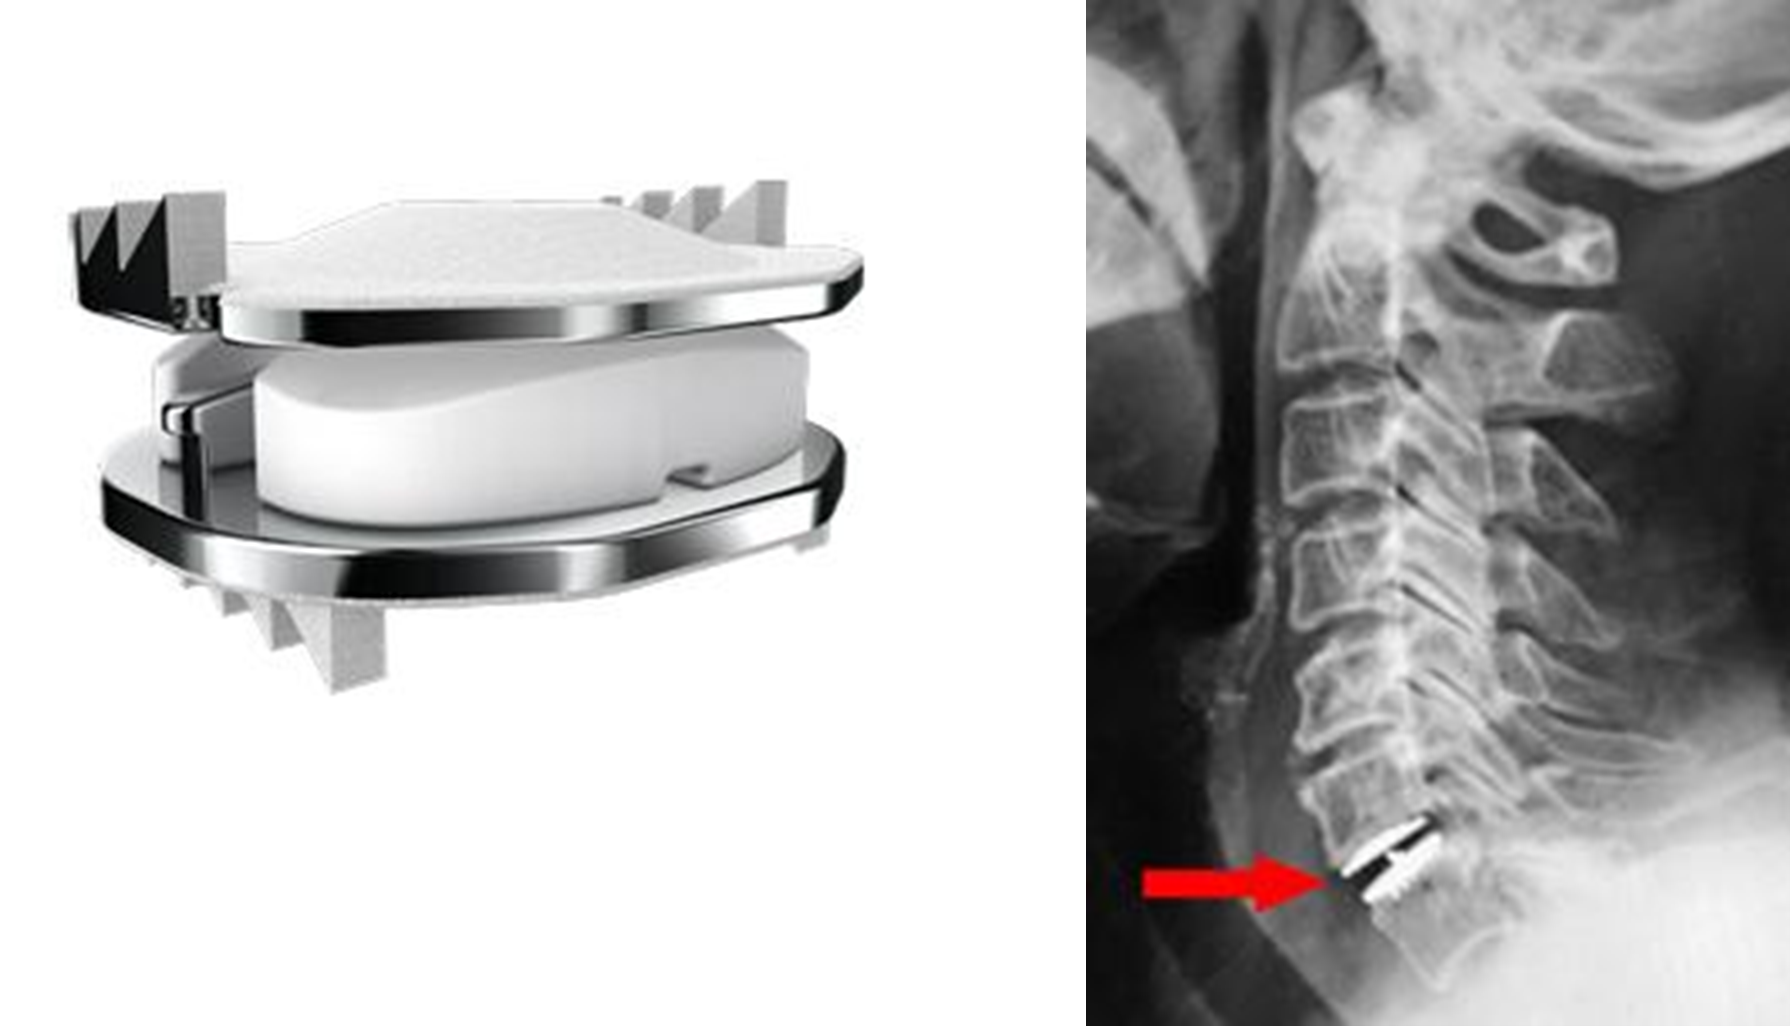

厚生労働省は、新たな医療機器の使用要件および基準の策定事業を実施しています。石井医師は、平成25年度(2013年)厚生労働省 次世代医療機器評価指標作成事業 脊椎インプラント分野 審査ワーキンググループに、平成28年度(2016年)厚生労働省 新医療機器使用要件等基準策定事業 頚椎人工椎間板置換術に対する使用基準作成ワーキンググループに参画し、本邦における頚椎人工椎間板置換術(TDR)の導入に際しての適正使用ガイドラインの作成に尽力しました。その後、TDRのインプラントが国内で正式に厚生労働省の承認を得て、2018年に国内第1例目となる頚椎人工椎間板置換術(ジンマーバイオメット社製・Mobi-C®)を実施致しました (図1、2)。

図(左)頚椎人工椎間板インプラント(Mobi-C®)

(右)術後レントゲン写真